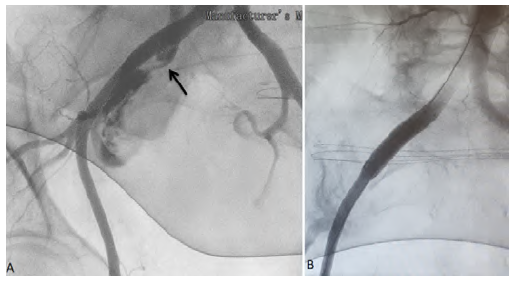

A 84-year-old female, with history of lupus, underwent pelvic exenteration, lymphadenectomy and cutaneous ureteroileostomy for high-grade urothelial carcinoma. In the postoperative period, an ileostomy with reconstruction of ureteroileal anastomoses and bilateral nephrostomies was required due to intestinal dehiscence with an abscess. She completed broad-spectrum antibiotics and antifungal therapy and was discharged with catheterized ureters. About 4 months later, the patient presented to the emergency department (ED) with gross hematuria. The blood work revealed 11g/dl of haemoglobin. Having been discharged, she returned to the ED the next day, hypotensive (94/61mmHg) with significant hematuria from ureteroileostomy, while haemoglobin had dropped to 8 g/dl, requiring aminergic support and the transfusion of two units of blood. Computed tomography (CT) angiography did not identify active bleeding and suggested integrity of the excretory system. She remained hospitalized under surveillance until she had another episode of hemorrhagic shock (blood pressure 49/23mmHg) with profuse bleeding through the ureteroileostomy, with a drop of hemoglobin to 5.5 g/dl. A new CT angiography was performed identified a fistula between the right common iliac artery and the ureteroileostomy (Figures 1 and 2). She underwent emergency angiography and fistula exclusion with a covered stent with intentional hypogastric coverage (the contralateral hypogastric was patent) given the short sealing length and the imminent risk of death (Figure 3). During the remaining hospital stay, there were no bleeding recurrences, and the patient was discharged on the 21st postoperative day after completing antibiotic therapy (meropenem and linezolid) and antifungal medication (micafungin) directed to urine cultures (isolated: multidrug resistant Staphylococcus aureus, Enterococcus faecium, Candida albicans). About one month later she was hospitalized again for acute kidney injury with ionic changes and complicated urinary tract infection, ending up dying from this complication.